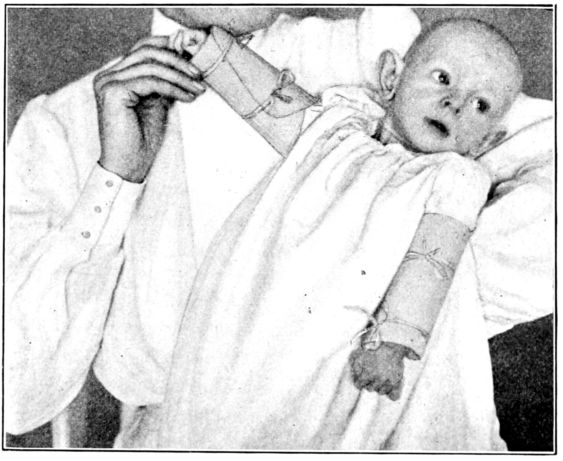

| 155. | Preparation for circumcision | 468 |

| 156. | Baby draped with sterile sheet, in above | 469 |